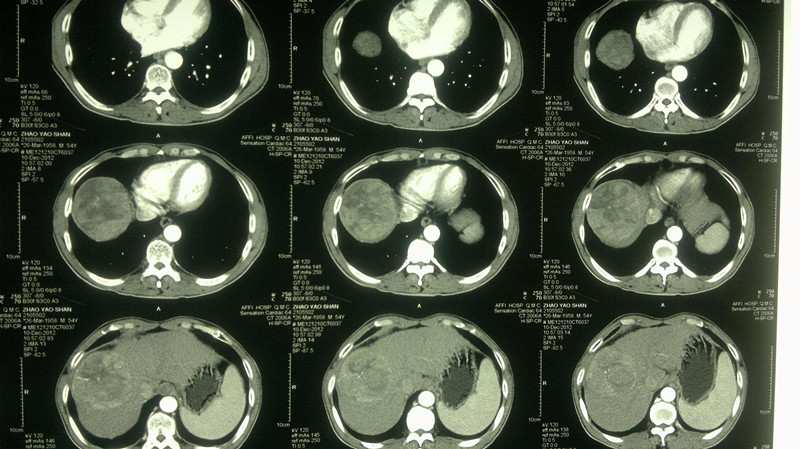

3. 肝腹水

正常人腹腔内有少量的游离腹水,一般为50毫升左右,起着维持脏器间润滑作用,当腹腔内出现过多游离液体时,称为腹水。(但是,这个病症比较少见,最常见的是肝硬化)。

6. 腹腔积液

正常状态下,人体腹腔内有少量液体(一般少于200ml),对肠道蠕动起润滑作用,超过200ml时,称为腹腔积液。比较常见的有心血管病、肝脏病、腹膜病、肾脏病、营养障碍病、恶性肿瘤腹腔转移、卵巢肿瘤、结缔组织疾病等,都有可能诱发腹腔积液。